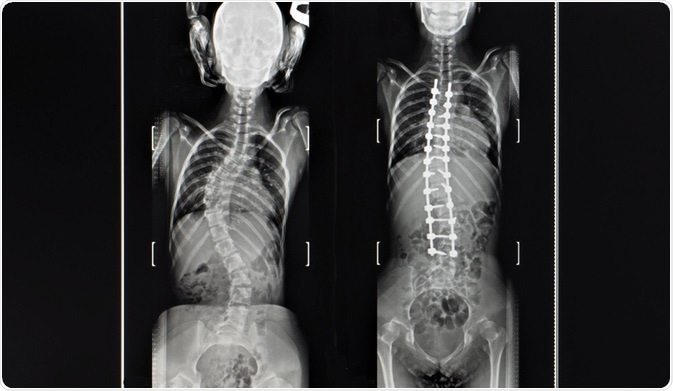

Particularly for young children with scoliosis, treatment may not be needed, as the condition may self-correct as the child grows. For this reason, observation is required to monitor the progression of the spinal curvature throughout growth and to intervene if the condition shows signs of worsening. X-ray images are often used as a method to monitor changes in the curve of the spine.

For children less than ten years old, growing rods can be inserted to help control the growth of the spine and may partially correct any existing damage. The rods will need to be monitored regularly and usually require lengthening two to three times per year as the child grows. These rods can later be removed when the adult height has been reached.

For teenagers or young adults, a spinal fusion may be needed in the treatment of scoliosis. This involves the straightening of the spine using metal rods and bone grafts to secure the spine in the correct positioning. This is considered to be a major operation and the rods typically remain in the patient's spine permanently as long as no problems arise.